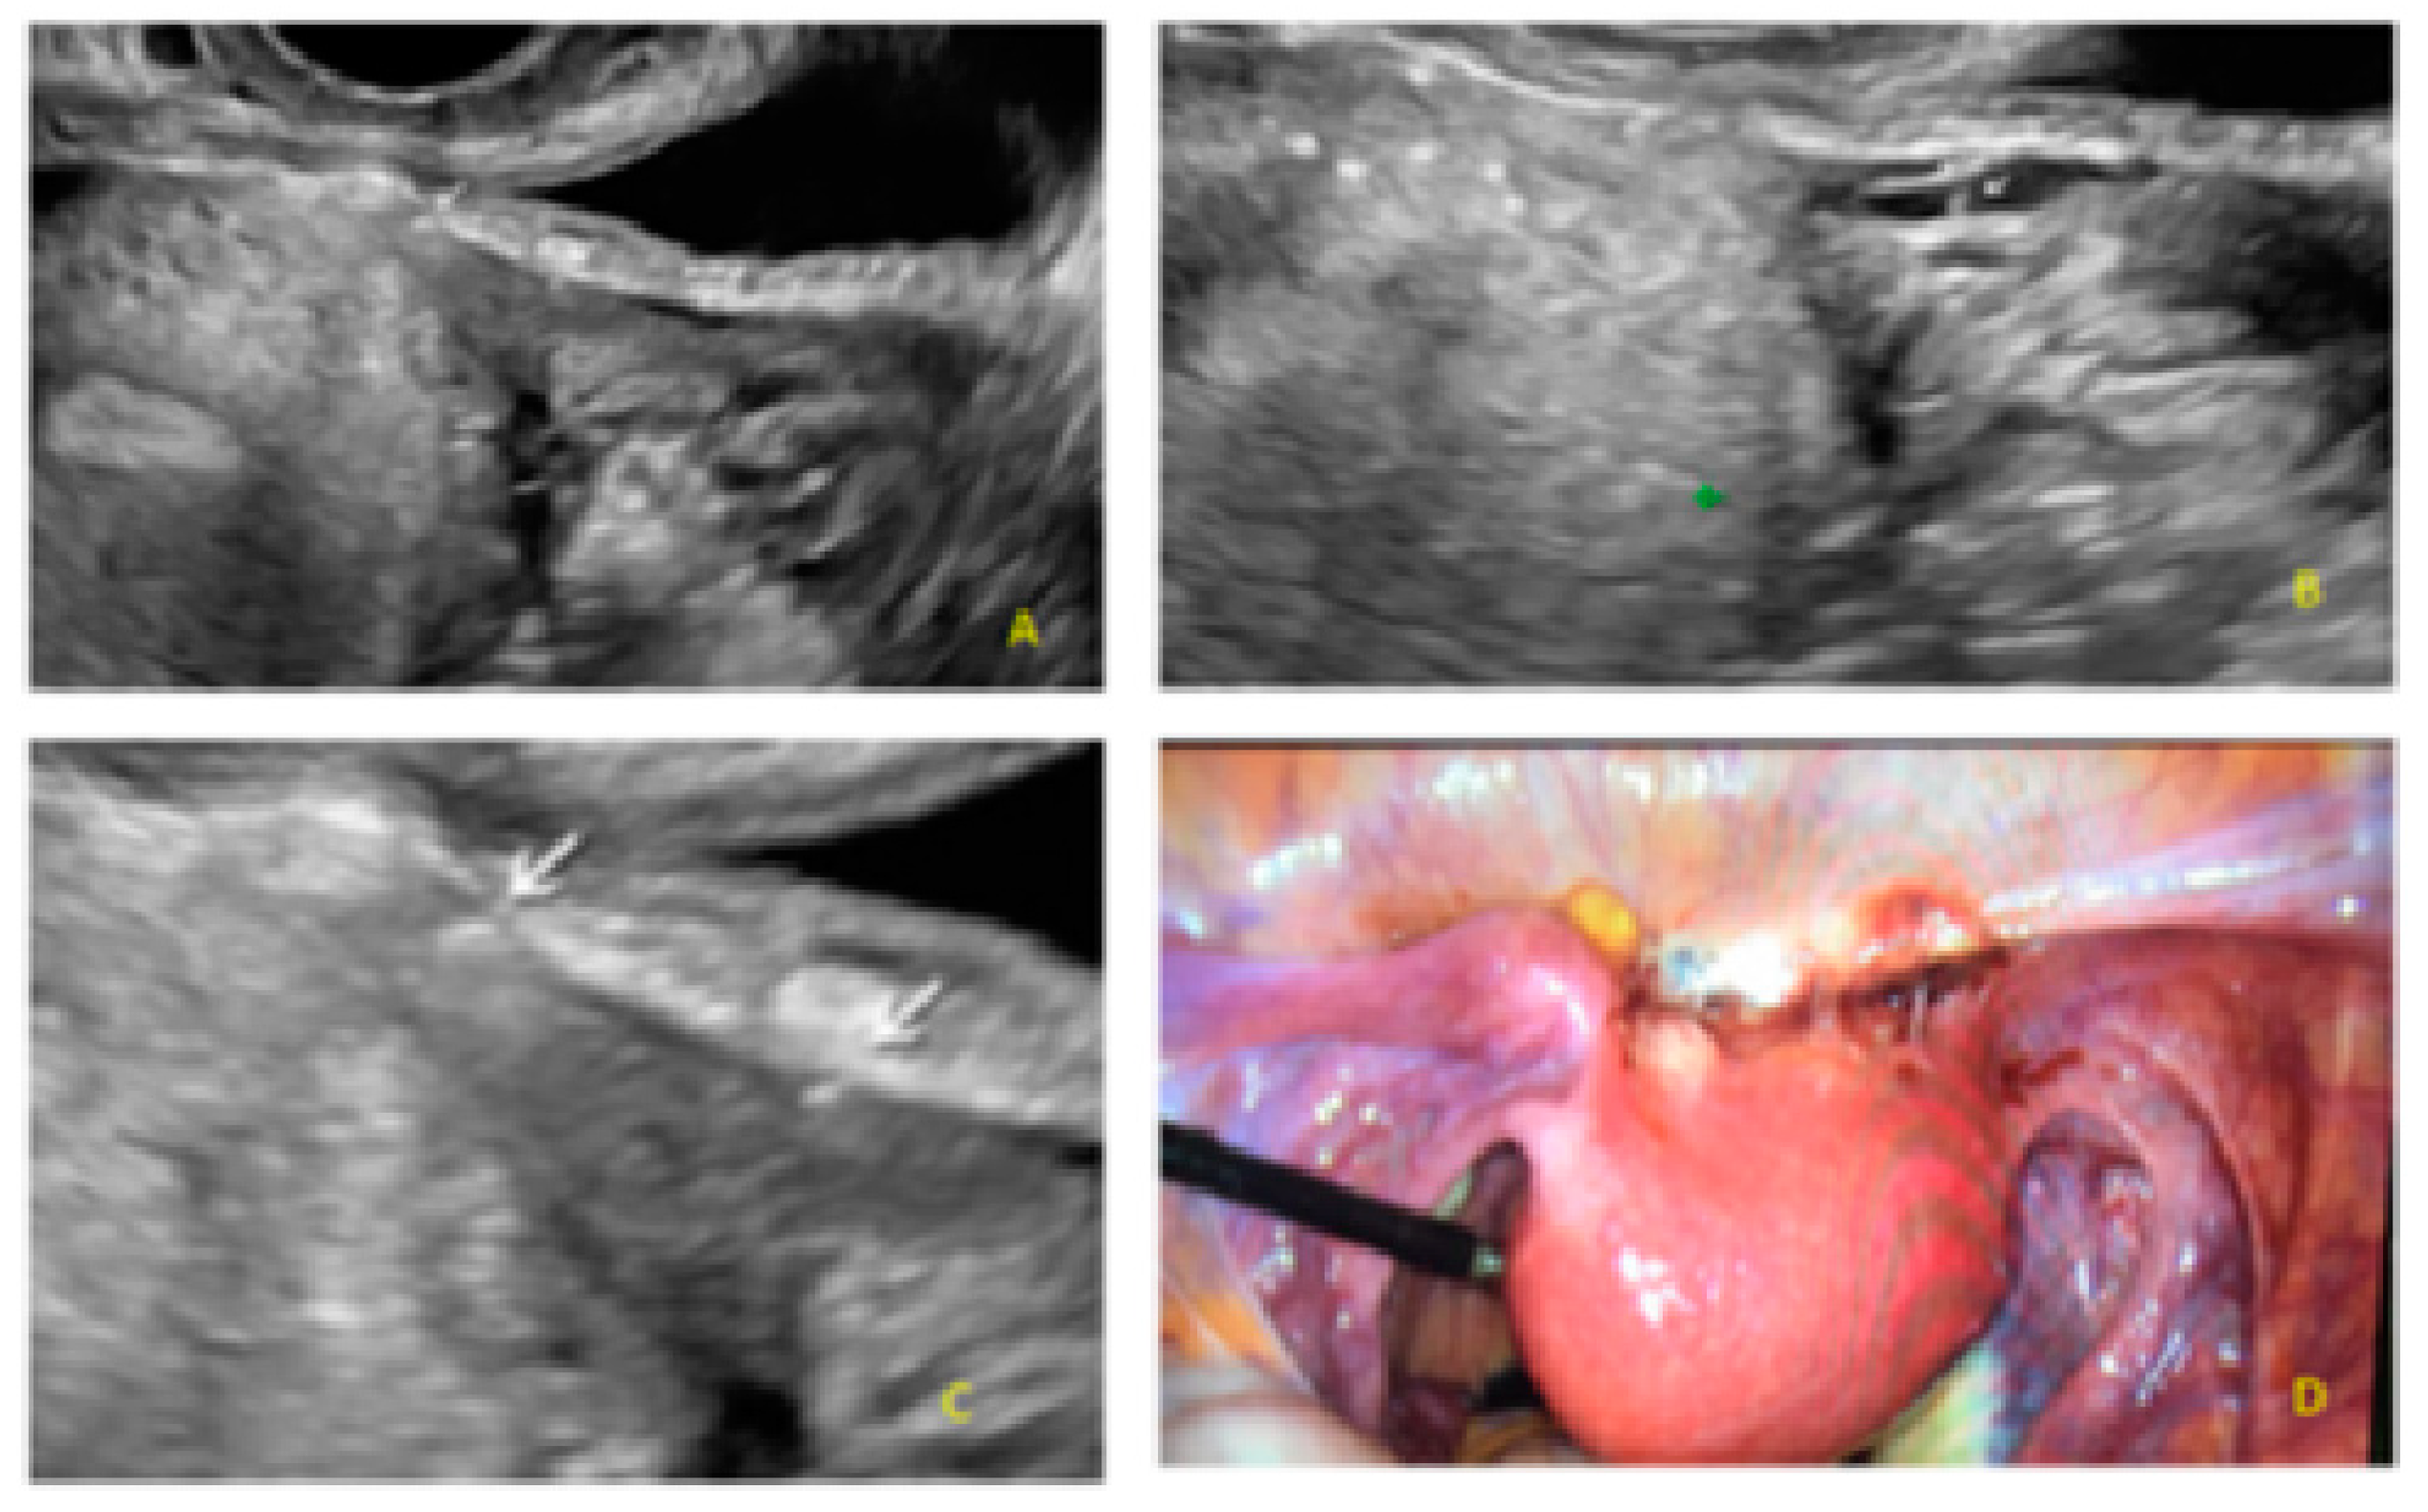

- The presence of hypoechogenic associated tissue (hypoechoic areas surrounding a small cyst area; we called this a “hat”). This tissue does not protrude or invaginate the peritoneal surface.

- The lesion may be convex, protruding from the peritoneal surface into the peritoneal cavity (we called this “bulging”), or it may appear as a concave defect in the peritoneum (we called this a “pocket”).

- The presence of hyperechoic foci (we called this a “pearl”).

- The presence of velamentous (filmy) adhesions associated to the lesion (we called this a “veil”).

3.1. Cystic Solitary Lesion